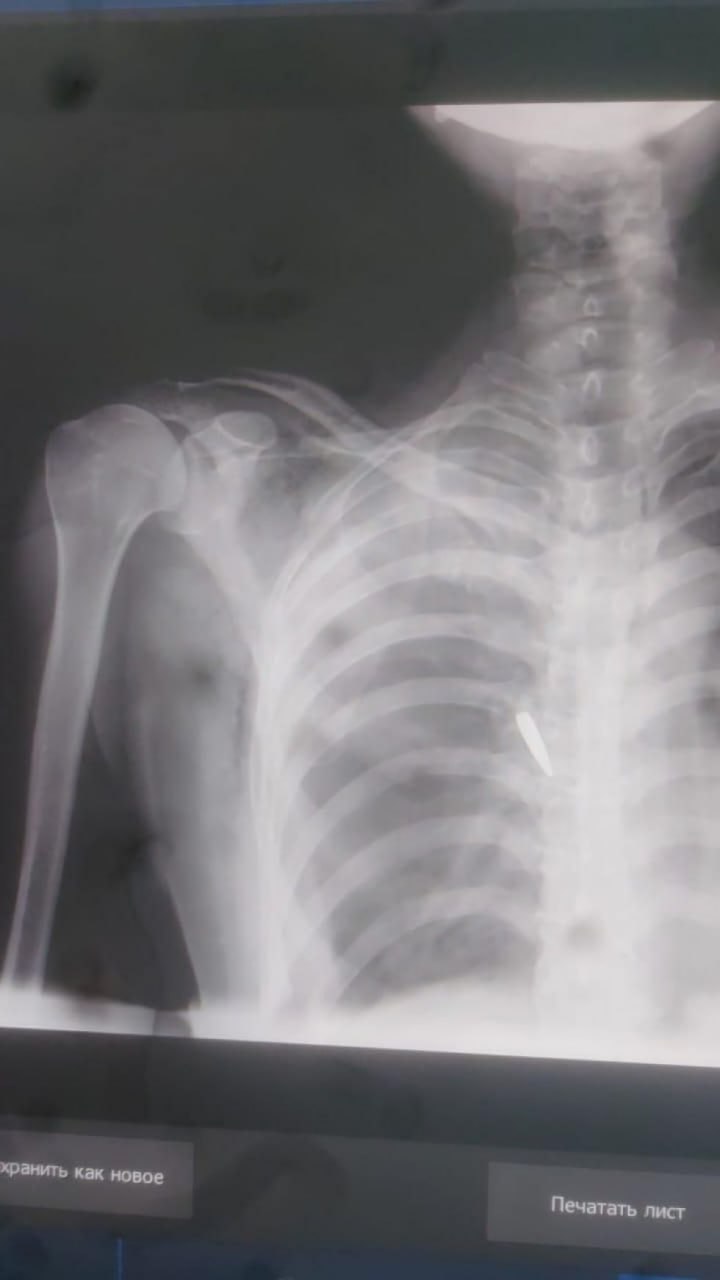

Как стало известно, пуля от автомата Калашникова прошла через плечо, повредила позвоночник, ребра, спинной мозг и лёгкие. Женщина перенесла сложную операцию, средства на которую (1,5 млн тенге) собрали военнослужащие. Как отметила Карсыбаева, помощь носила частный характер и не была официальной выплатой со стороны министерства обороны.

В результате травм пострадавшая получила инвалидность II группы и теперь вынуждена носить поддерживающий корсет. Она воспитывает троих детей и сталкивается с проблемами из-за утраты трудоспособности.